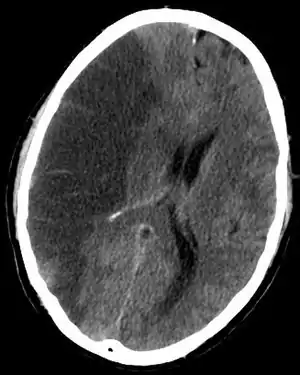

| CT scan slice of the brain showing a right-hemispheric cerebral infarct (left side of image). | |